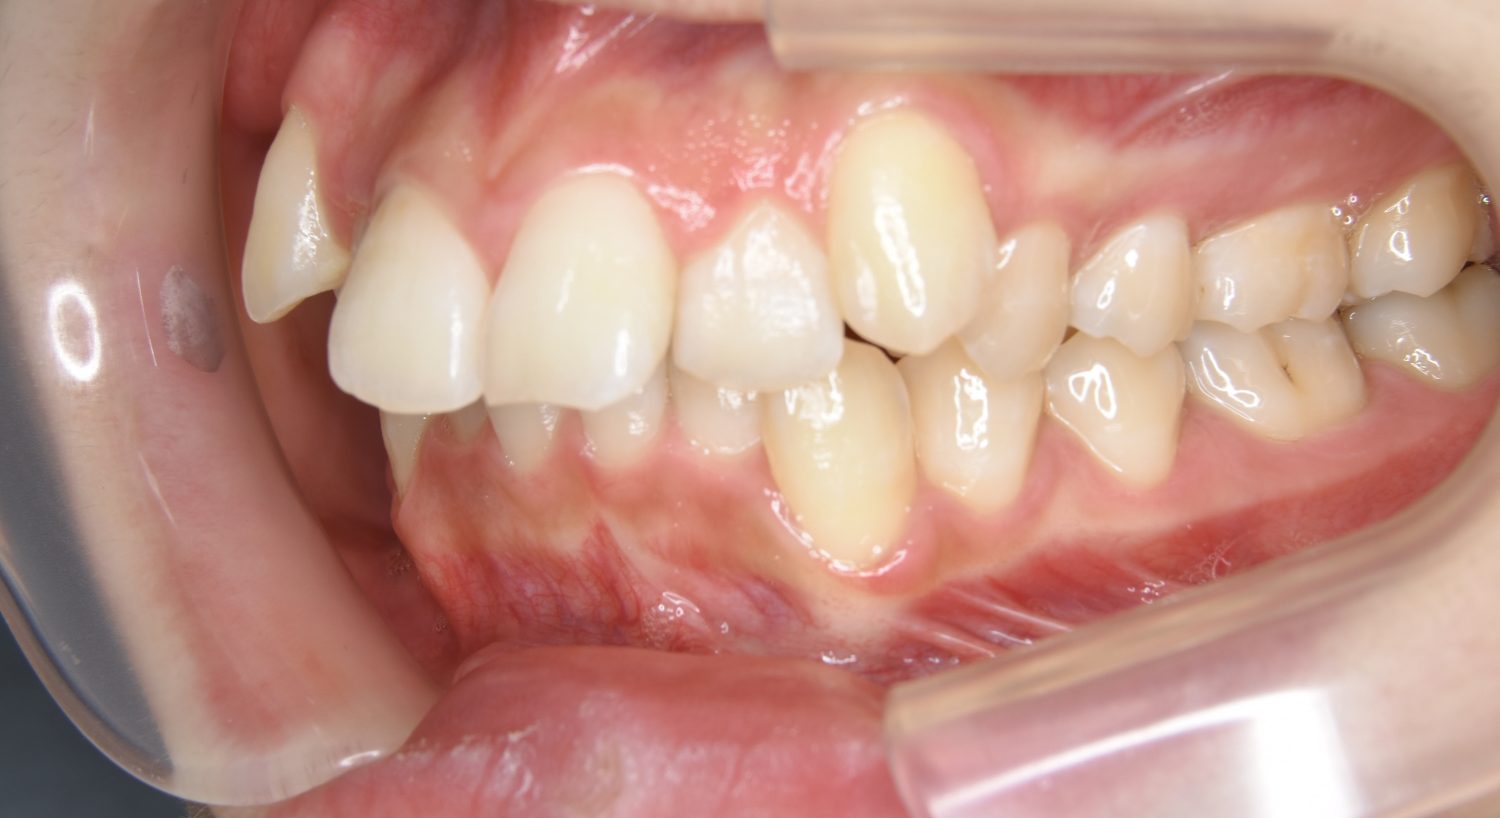

叢生の症例紹介②

Before

After

主訴

歯の凸凹を治したい。

治療内容

アライナー(インビザライン)にて非抜歯で治療を行いました。

治療費

1,150,000 円(税込)

治療期間

26ヶ月

通院回数

14回

想定されたリスク

※歯根吸収、歯肉退縮、歯髄壊死、顎関節症状

※アライナー(インビザライン)は日本の薬機法未承認の矯正装置であり、医薬品副作用被害救済制度の対象外となる場合があります。

丸山和宏先生

ピーススマイル矯正歯科

上下前歯部に叢生(凸凹)が認められる状態でした。歯列の遠心移動を行うことで機能面および審美面が改善されました。